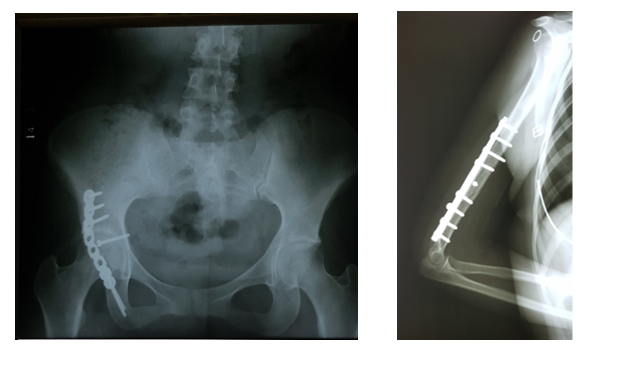

FRACTURA DE ACETABUL O DERY HÚMERO IZQUIERDO